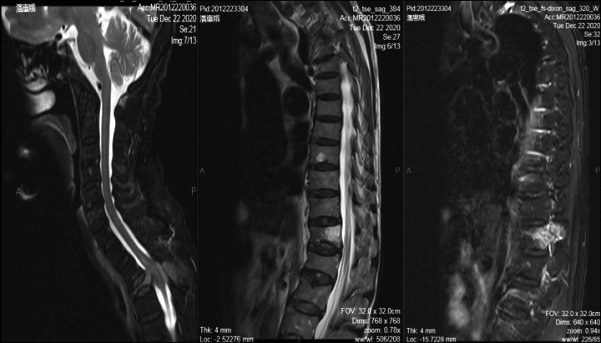

王某,男,78岁,去年国庆节前后出现轻微腰背部疼痛,没有在意,也没有进行治疗,症状时轻时重。 去年年底,王某突然出现双下肢无力,腰背部疼痛逐渐加重,10天后行走困难。 王某来到郑州市中心医院就诊时,已经不能行走,是坐着轮椅来的。王某入院后,进行了一系列检查。根据他的检查结果,我诊断是前列腺癌脊柱转移,他的前列腺癌指标PSA(前列腺特异性抗原)极高。王某发生前列腺癌脊柱转移,以胸椎为主,并压迫脊髓神经,导致瘫痪。 我给患者仔细讲述了病情以及导致瘫痪的原因,并讲明了手术治疗的必要性。 我带领郑州市中心医院脊柱外科医生,给患者实施了椎管减压和脊柱重建术。术后,患者不仅疼痛减轻,而且下肢活动功能明显改善,半个月后可以下床走路。 患者出院后,半个月来郑州市中心医院复查一次。我给予患者抑制肿瘤骨转移治疗,主要是进行比卡鲁胺抗雄激素治疗和二膦酸盐抗骨转移治疗。经过治疗,患者行走自如,能干家务活,每月的治疗费用不到1000元。患者多次来到我们医院进行复查,原有骨转移范围未扩大。 肿瘤转移(常见转移部位有脑、膈、淋巴结等)是恶性肿瘤的一个特征,并且是一个很不好的特征,而骨组织是恶性肿瘤转移的好发部位。肿瘤骨转移是指骨头以外的恶性肿瘤细胞,通过血流转移或者局部直接侵犯的方式转移到骨内。 肿瘤骨转移发生后,一部分患者无任何症状,但也有一部分患者会感到剧烈疼痛,发生病理性骨折、椎体塌陷,甚至压迫脊髓神经,引起瘫痪,让患者承受非常大的痛苦,严重影响患者的生活质量。 肿瘤骨转移及其造成的并发症也会导致治疗的难度增加及护理困难。让肿瘤患者少受肿瘤骨转移的“折磨”,保持不畏惧、积极治疗的心态,很重要。对肿瘤骨转移,早预防、早发现、早治疗是正确的做法。 虽然疼痛是肿瘤骨转移的一个主要症状,但是也有一部分肿瘤骨转移患者无任何痛苦的表现。除此之外,肿瘤骨转移患者还可能出现病理性骨折、高钙血症、肾结石等一系列并发症,如果发生脊柱转移,甚至会引起瘫痪。 大多数恶性肿瘤会出现骨转移,主要以前列腺癌、乳腺癌及肺癌为主。大约72%的前列腺癌患者、58%的乳腺癌患者、53%的肺癌患者会发生骨转移,其他常见的还有大肠癌、肾癌、胃癌、女性生殖系统癌等。 肿瘤发生骨转移的部位以脊柱最多,其次为肋骨、骨盆,而四肢骨少见。 一般来说,肿瘤骨转移早期是没有任何症状的,很多患者都是在肿瘤骨转移后期才出现剧烈疼痛,俗称“蚀骨之痛”。大多数肿瘤骨转移患者会有疼痛,疼痛是肿瘤骨转移患者面临的最大难题。在临床上,有些人是因为骨痛才去医院就诊,从而发现肿瘤骨转移;有些人发现肿瘤骨转移不是因为骨痛,而是因为骨折。 不同部位的肿瘤骨转移也有不同的疼痛症状:转移到脊柱时,表现为后背部正中或病变部位疼痛,压迫脊髓神经时可出现瘫痪;转移到肋骨时,表现为胸壁局限的、有明确压痛点的疼痛;而转移到骨盆、四肢骨时,表现为这些部位有局限性疼痛及放射性疼痛。 疼痛、骨折、瘫痪等一系列症状除了会给患者带来痛苦外,也会严重影响患者的饮食、睡眠质量。有些患者在经历疼痛→失眠→疲乏→疼痛→失眠→疲乏这样的恶性循环后,可能会产生不同程度的焦虑抑郁和营养不良。因此,对于出现肿瘤骨转移的患者来说,控制骨痛是一个非常重要的治疗目标。 肿瘤骨转移能否预防?答案是肯定的。 研究表明,双膦酸盐可以有效降低肿瘤骨转移相关并发症的发生率。多个临床试验结果显示,对于绝经后的乳腺癌患者,使用双膦酸盐能够降低乳腺癌骨转移的发生率,还有助于降低患者的死亡率。乳腺癌相关治疗指南指出,对于早期乳腺癌患者,建议应用双膦酸盐进行早期干预。 放射性核素锶-89有助于缓解患者骨痛和提高患者的生活质量。放射性核素锶-89虽然为全身给药,但是静脉注入后,在骨转移灶或骨肿瘤部位会出现较高浓度的聚集,是一种可有效治疗肿瘤的内照射治疗剂。前列腺癌、乳腺癌、肺癌等晚期肿瘤患者很容易发生骨转移,会有剧烈骨痛,严重影响患者的生活质量,而放射性核素锶-89可聚集于骨转移灶内,利用其发射的β射线进行内照射,达到杀死肿瘤细胞、抑制肿瘤骨转移的目的,并有效缓解疼痛,有效率达80%以上。一次治疗,止痛效果可以达3个月~6个月。 地诺单抗在防治肿瘤骨转移上也有很好的效果,它可以抑制肿瘤生长,使肿瘤区域骨化,对于高级别的、不可切除的、转移性的肿瘤疗效显著,主要用于实体瘤骨转移患者中骨骼相关事件的预防。地诺单抗适用于有骨质疏松症的绝经期妇女、雄激素阻断治疗所致的前列腺癌患者、芳香化酶抑制剂治疗所致的乳腺癌患者。 肿瘤骨转移能否早发现,答案也是肯定的。 恶性肿瘤患者应坚持每半年做一次骨扫描和PET-CT(正电子发射计算机断层显像)检查。SPECT-CT是单光子发射型计算机断层成像系统和X线计算机断层扫描成像系统一体化组合的影像诊断设备,能完美显示脏器组织的形态及功能变化,从而更早发现脏器功能及形态学变化,对某些疾病做出准确诊断,精准定位。PET-CT检查不仅适用于骨,而且适应于软组织(如肺部),和SPECT-CT检查的侧重点不一样。全身骨显像可以早期诊断骨转移瘤,比X线检查提前3个月~6个月发现病灶。 PET-CT是把正电子发射体标记的葡萄糖、氨基酸、胆碱、胸腺嘧啶及血流显像剂等药物作为示踪剂,以解剖图像的方式,用分子水平显示机体及病灶组织细胞的代谢、功能、血流、细胞增殖和受体分布情况,为临床提供更多的生理和病理方面的诊断信息,故也称为分子显像。 PET-CT有以下作用:可以对肿瘤的良性、恶性进行鉴别诊断;进行肿瘤的临床分期及治疗后再分期;对肿瘤治疗过程中的效果进行监测,对治疗后的效果进行评价;在肿瘤患者随访过程中监测肿瘤复发及转移;对肿瘤治疗后的残余与治疗后的纤维化或坏死进行鉴别;已发现肿瘤转移而临床需要寻找原发灶。患者进行PET-CT检查,有利于医生制定最佳治疗方案,发现早期肿瘤癌前病变,以获得治愈的机会。 除此之外,还可以通过监测血中碱性磷酸酶,尽早发现可能存在的骨转移。